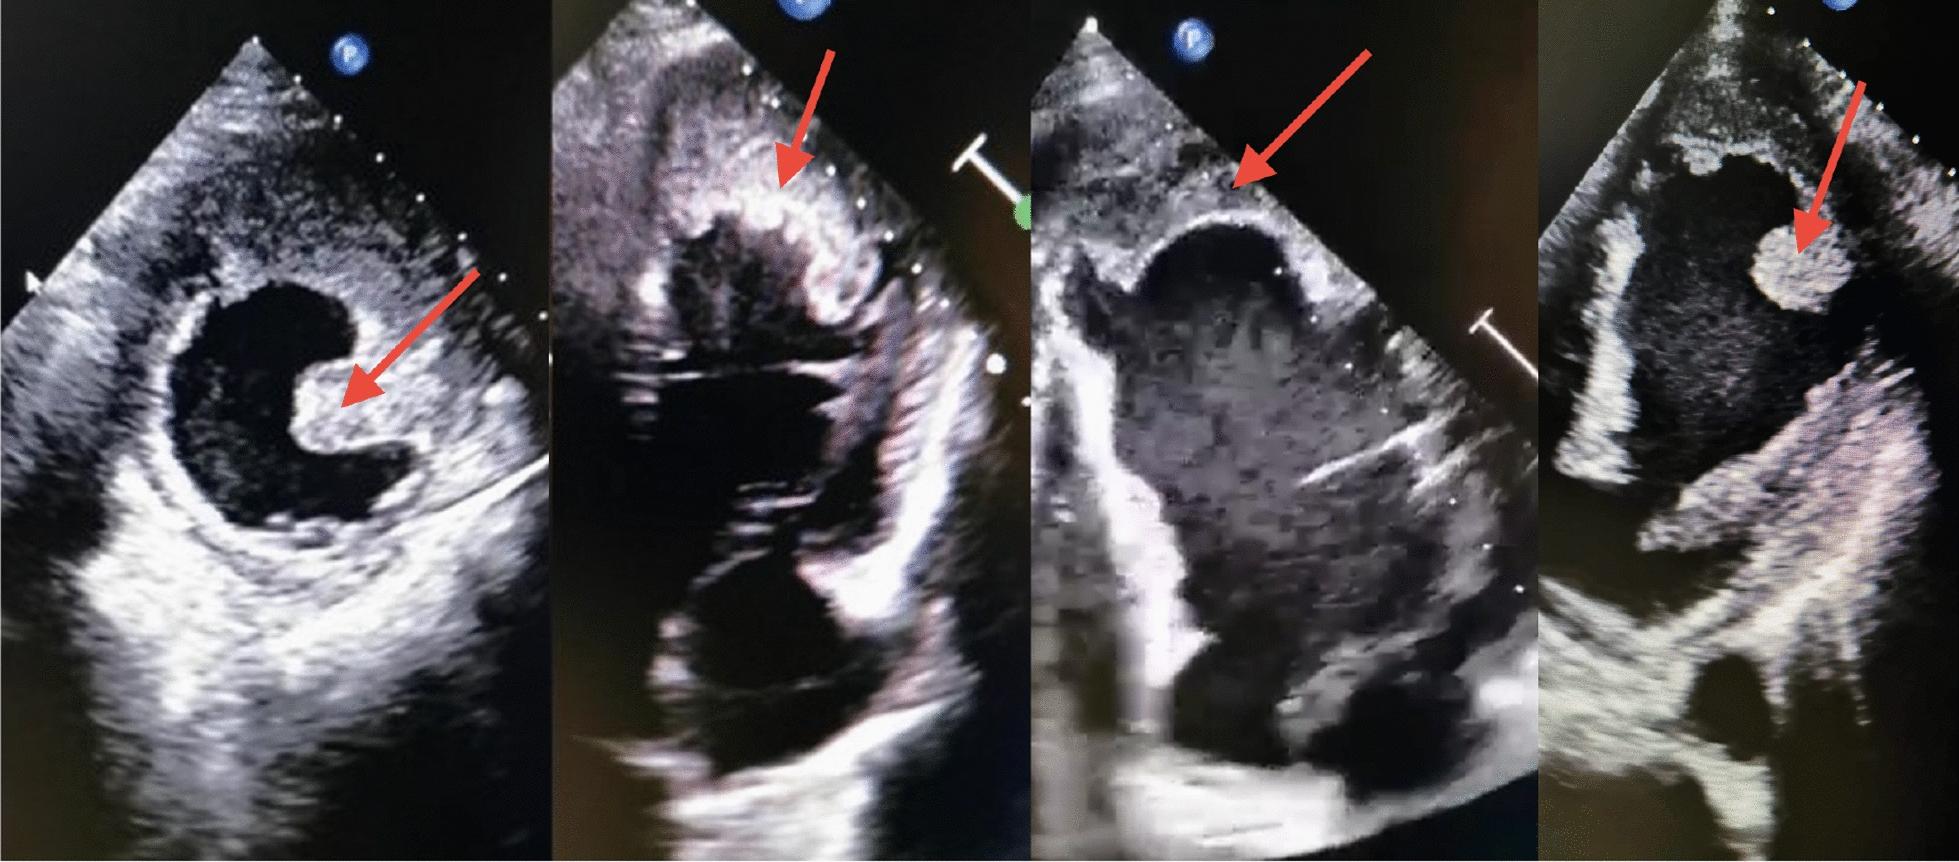

In this paper, we present two White male patients of Central European (Polish) descent (50 and 64 years old) who, although reported to have had acute ST-elevation myocardial infarction, turned out to be ST-elevation myocardial infarction latecomers. In both cases, we were dealing with the presence of left ventricular thrombus and complications related to the central nervous system. On the basis of these two patients, we discuss the role of revascularization in latecomer ST-elevation myocardial infarction patients. We present the position of direct oral anticoagulants in the left ventricular thrombus treatment and show that, in limited cases of a huge thrombus, cardiac surgery is a treatment of choice.

在本文中,我们介绍了两名中欧(波兰)血统的白人男性患者(分别为50岁和64岁),他们虽被报告患有急性ST段抬高型心肌梗死,但实际上是ST段抬高型心肌梗死的延迟就诊者。在这两个病例中,均存在左心室血栓以及与中枢神经系统相关的并发症。基于这两名患者,我们讨论了血运重建在延迟就诊的ST段抬高型心肌梗死患者中的作用。我们阐述了直接口服抗凝剂在左心室血栓治疗中的地位,并表明在巨大血栓的有限病例中,心脏手术是首选治疗方法。